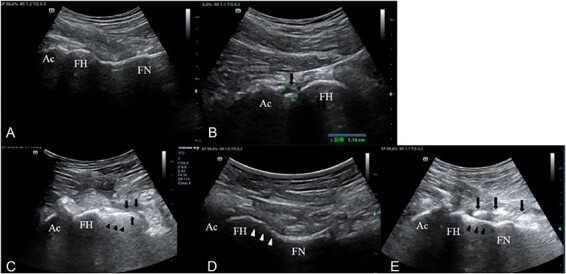

本研究旨在评估术中超声监测骨软骨成形术的可行性,确定干扰超声成像的因素,并评估其对外科医生表现的影响。对39例关节镜下骨软骨成形术进行术中超声检查。超声检查股骨头颈结(FHNJ)。另外39例患者行常规关节镜检查作为对照组。本组在骨软骨成形术结束时使用c型臂,以确认没有残留的凸轮病变。分析术前和术后Dunn x线片和计算机断层扫描(CT)以确定超声的可行性。超声检查发现8例残cam畸形。在3例中,由于空气的超声干扰,未检测到FHNJ。两组在1:00、2:00、3:00位置的Dunn片α角测量值及CT残cam畸形率均无差异。超声组3:00位α角明显大于对照组(44.4±4.3°比41.3±5.1°,P

This study aimed to evaluate the feasibility of using ultrasound for monitoring osteochondroplasty intraoperatively, determine the factors that interfere with ultrasound imaging and assess its influence on surgeon performance. Intraoperative ultrasonography was performed during osteochondroplasty in 39 cases of arthroscopy. The femoral head-neck junction (FHNJ) was evaluated using ultrasonography. Another 39 cases, which underwent conventional arthroscopy, were included in the control group. The C-arm was used in this group at the end of osteochondroplasty to confirm that no residual cam lesion remained. Pre- and postoperative Dunn radiographs and computed tomography (CT) scans were analyzed to determine the feasibility of ultrasound. Residual cam deformity was noted in eight cases under ultrasound. The FHNJ was not detected owing to ultrasound interference by air in three cases. No difference in the α angle measured in Dunn radiographs and the residual cam deformity rate of CT at the 1:00, 2:00 or 3:00 position was found between both groups. However, the α angle at the 3:00 position was greater in the ultrasound group than in the control group (44.4 ± 4.3° versus 41.3 ± 5.1°, P < 0.05), suggesting that more bone was preserved at 3:00 in the ultrasound group. No difference was found in the mean operation time. None of the patients experienced complications, such as wounds or intra-articular infections. Ultrasound is a safe method for assessing FHNJ during arthroscopy. It did not change the risk of residual cam deformity but positively affected the surgeon's performance by reducing unnecessary bone removal.